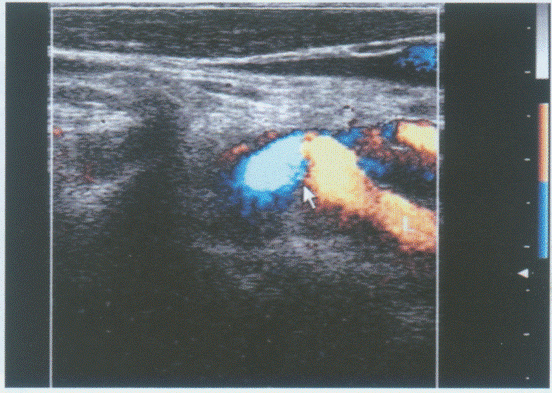

患者颈部肿大,可扪及肿块。如图,提示为()。

A.甲状腺腺瘤

B.结节性状腺肿大

C.甲状腺癌